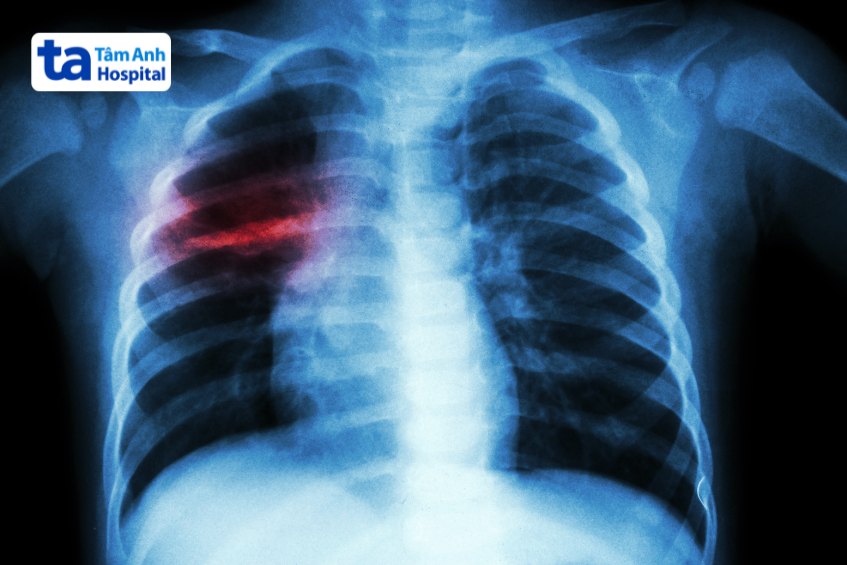

Hình ảnh tổn thương trên Xquang phổi nghi lao.

Trẻ cũng có thể cần chụp X-quang phổi, xét nghiệm đờm, hoặc sinh thiết các hạch bất thường hoặc mô cơ thể khác.

Có kết quả X-quang phổi nghi ngờ bệnh lao.

Chẩn đoán bệnh lao phổi trẻ em bằng X-quang.